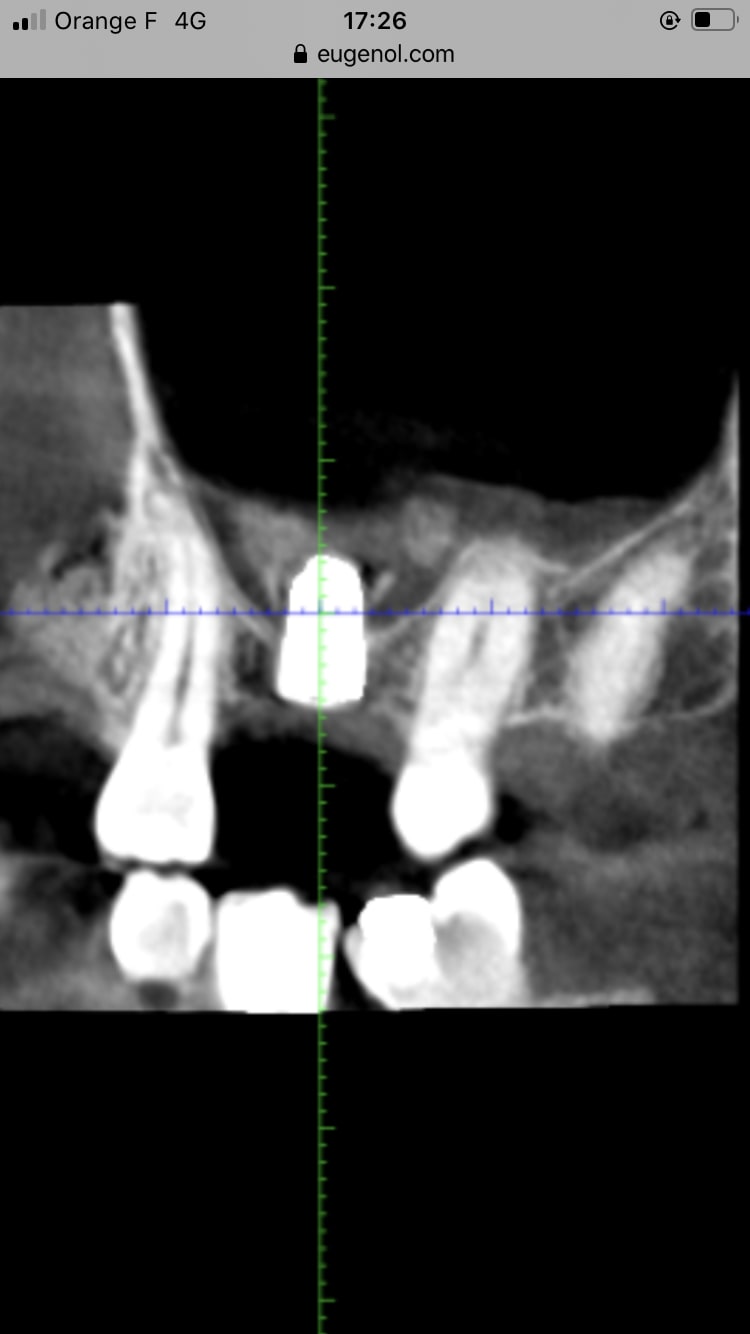

J'ai posé un implant via un summers ( 2-3mm d'os de base et implant 5x8 ) sur 26 et lors du controle post 3 mois je vois que la majorité du bio oss à disparu ( il reste quelques zones par ci par là)

et voila la radio

Honnêtement Je le sens pas ton truc :) je pensais que l’implant reposait complètement dans le vide sans rien autour. Là tu n’as pas que du bio oss autour. C’est de la fibro intégration sur les 2/3.

je peux me tromper, mais je ne pense pas voir un granulome à l'apex de l'implant mais une muqueuse hyperhémiée ou congestionnée, au dessus d'une zone osseuse qui me parait saine et semble faire plus de 2/3 mm..